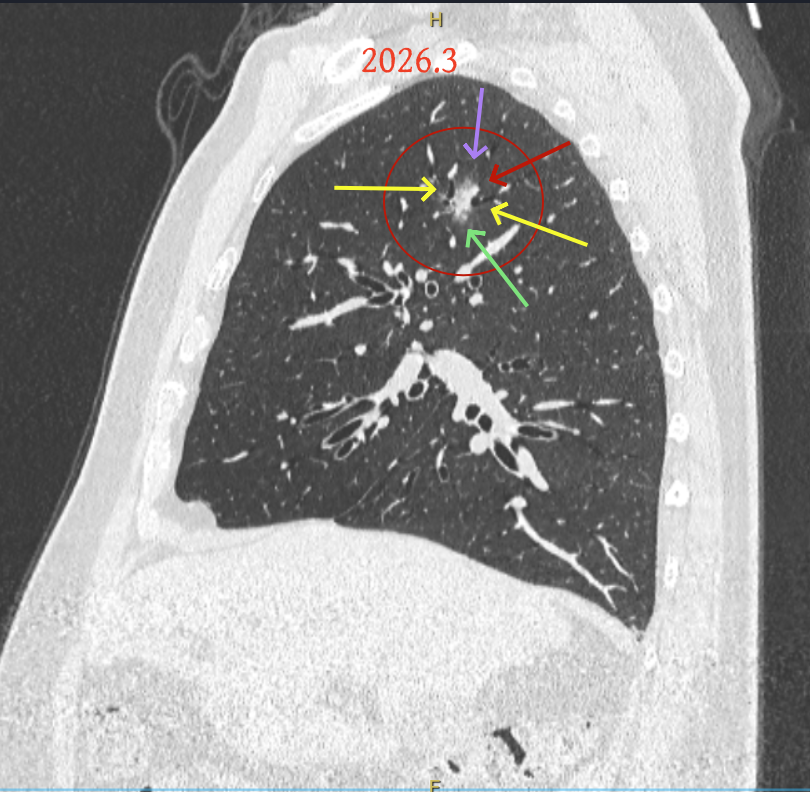

第三次问诊:2026.3

影像展示与分析:

但病灶B却显然进展!变成以实性成分为主的了!

再看2026年3月最近复查时不同层面病灶A的细节影像特征:

微小血管走向病灶,磨玻璃的密度淡而较纯。

再看病灶B的2026年3月细节影像特征:

边缘位置也是较淡的磨玻璃成分。

上图是混合密度,轮廓较清,瘤肺边界欠清晰。

病灶A以及他处磨玻璃结节其实进展都是不明显的,略与2022年比,病灶A稍显明显点。病灶B开始时极淡,之前进展虽有但也甚微,直到2025年9月仍是磨玻璃成分为主,只是点状少许密度稍高成分。但在最近半年内却显然进展!若从影像上判断,基本上就得是浸润性腺癌了。那有几点:一是必不能再随访;二是大小来看仍是1A期;三是从快速进展来说,可能含有部分高危亚型,比如微乳头或实体型等;四是他处的磨玻璃结节以及病灶A显然不能用病灶B的转移来解释,仍考虑是多原发早期肺癌。

结友问能否先穿刺?我是这么考虑的:你这个病灶B一是位置深,且靠近附近的血管,不容易穿刺;二是从影像变化来看,基本上肯定是恶性的,不是100%,也是95%以上的概率。刚才我又在重建看冠状位与矢状位以及各次影像,目前混合密度的其实是后来者居上,原来刚开始是它比旁边的病灶密度淡的,但它的密度不是太纯,前次你自己也说似乎有点状偏实性成分。只是最近这半年进展特别快。这说明它的恶性程度较它边上原来就比较明显的那处恶性程度高,亚型中大概率有低分化的成分。所以从目前的影像来看,要尽快手术,而且切肺叶更为稳妥些。

这是较为少见的一个病例,磨玻璃为主,而且一直瘤肺边界欠清晰的病灶何以会在之前三年均极缓慢微小变化的情况下,近半年却快速进展呢?从影像细节上看,我们能否进一步分析哪种纯磨玻璃结节可能会较快进展?结合本例,我个人的考虑是:1、病灶整体显得是磨玻璃密度,但灶内并不均匀,就如磨玻璃密度中混入细沙状;2、整体轮廓虽然较清但瘤肺边界相对来说却并不太清晰;3、邻近有血管紧挨,而且与病灶这间缺乏间隙;4、病灶密度不高,没有明显实性成分,却有灶内有细支气管通气征,说明肿瘤成分具有收缩力,却与纯磨的收缩不匹配(纯磨一般不太会有明显收缩力)。如果有上面这些特征可能要提高警惕,一是适当较短的随访间隔,二是影像细节变化要更加注意,开始变化意味着已经进入发展期,而非蛰伏期。当然是否在2025年9月时定得手术了?如果是孤立性的病灶B,且位置位于能简单楔形切除的位置,那是可以考虑的。但位置深、两肺多发,切除范围不小,再今年据肺癌诊疗指南中说的混合磨玻璃结节实性成分不足25%是非侵袭性病变,且几乎不会转移,那么按原则仍再随访显然是可以的。本例的随访变化再次表明磨玻璃密度肺癌的诊疗个体化之路仍是很漫长的,按指南原则的随访或诊疗显然不足以覆盖所有病例,总结与经验积累永远在路上。